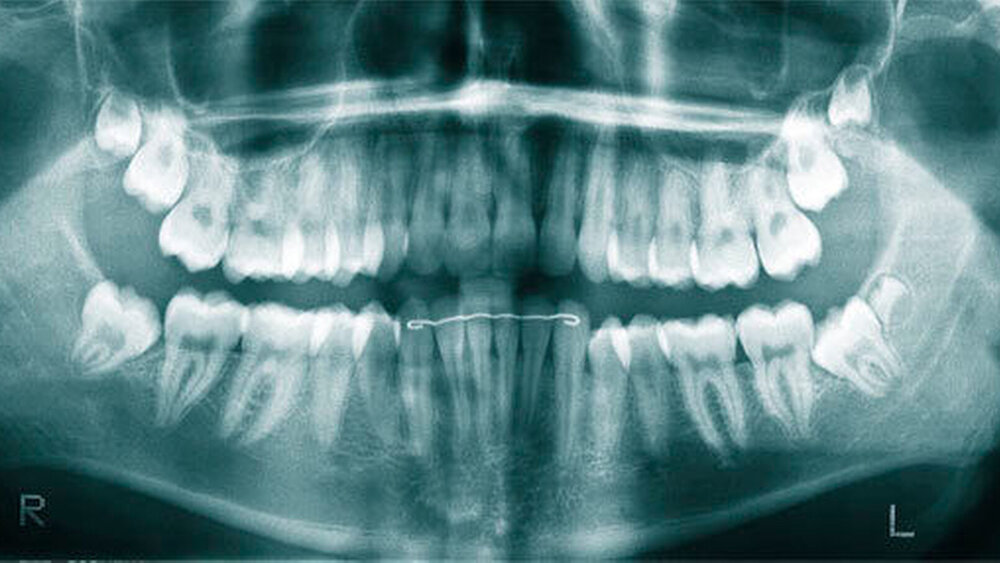

Überzählige Zähne werden nach ihrer Lage im Zahnbogen und auch aufgrund ihrer Morphologie eingeteilt. Basierend auf der Lage unterscheidet man bei überzähligen Zähnen zwischen Mesiodens (Oberkiefer median), zwischen den zentralen Inzisiven (Abbildungen 5 und 6), einem zusätzlichen Schneidezahn (zentral oder lateral), Eckzahn, Prämolar (Abbildung 7), Paramolar und Distomolar (Abbildungen 8). Mesiodentes werden am häufigsten dia- gnostiziert, wobei Prozentsätze zwischen 38,8 Prozent bis 86,3 Prozent der überzähligen Zähne in der Literatur zu finden sind [Salcido-García et al., 2004/38,8 Prozent, Fernández Montenegro et al., 2006 /46.9 Prozent; Mossaz et al., 2014/48.5 Prozent; Ferrés-Padró et al., 2009/53.2 Prozent; Schmuckli et al., 2010/75 Prozent; Rajab Hamdan 2002/83.2 Prozent; Liu et al., 2007/86.3 Prozent]. Überzählige Prämolaren und seitliche Schneidezähne sind die zweithäufigste Gruppe der überzähligen Zähne. Überzählige Eckzähne, Paramolaren und Distomolaren dagegen gelten als eher selten [Rajab Hamdan, 2002; Salcido- García et al., 2004; Liu et al., 2007; Ferrés-Padró et al., 2009; Schmuckli et al., 2010; Mossaz et al., 2014]. Einzig eine Spanische Gruppe [Fernández Montenegro et. al., 2006] berichtete, dass Paramolaren und Distomolaren insgesamt relativ häufig seien (18 Prozent, beziehungsweise 5,6 Prozent). Überzählige Zähne kommen im Ober- und Unterkiefer vor, wobei sich überzählige Schneidezähne in der Regel im Oberkiefer, überzählige Prämolaren sich dagegen eher im Unterkiefer befinden [Fernández Montenegro et al., 2006; Ferrés-Padró et al., 2009; Mossaz et al., 2014]. Überzählige Molaren wiederum treten normalerweise im Oberkiefer auf [Cassetta et al., 2014; Kaya et al., 2014].

Bei überzähligen Zähnen werden vier morphologische Typen unterschieden: konisch (Abbildung 9), tuberkulär (höckerförmig; Abbildung 10), überzählige Zähne mit identischer Zahnform (Abbildung 11) und Odontom (Abbildung 12) [GARVEY et al. 1999]. Der konische überzählige Zahn ist ein kleiner, zapfenförmiger Zahn und zudem der häufigste Fall im bleibenden Gebiss [Rajab Hamdan 2002, Liu et al. 2007, Gündüz et al., 2008; Ferrés-Padró et al., 2009; Hyun et al., 2009; Schmuckli et al., 2010; Mossaz et al., 2014]. Er kommt oft zwischen den oberen zentralen Schneidezähnen vor und entwickelt sich gleichzeitig zur Wurzelbildung der bleibenden Schneidezähne. Konische überzählige Zähne führen meist nicht zu einer Durchbruchstörung oder -behinderung der zentralen Schneidezähne. Tuberkuläre, überzählige Zähne sind größer als der konische Typ und besitzen einen zusätzlichen charakteristischen Höcker oder Tuberkel der Zahnkrone. Sie kommen oft gepaart vor und liegen in der Regel palatinal der oberen mittleren Schneidezähne. Im Gegensatz zu konischen überzähligen Zähnen brechen die meisten tuberkulären nicht in die Mundhöhle durch und es kommt nicht selten zur Durchbruchstörung oder -behinderung der zentralen Schneidezähne [Mason et al., 2000; Minguez-Martinez et al., 2012]. Überzählige Zähne mit identischer Zahnform sind Zähne, welche vom eigentlichen Zahn in der Lage (also in der Zahnreihe gelegen) und Form nicht zu unterscheiden sind.